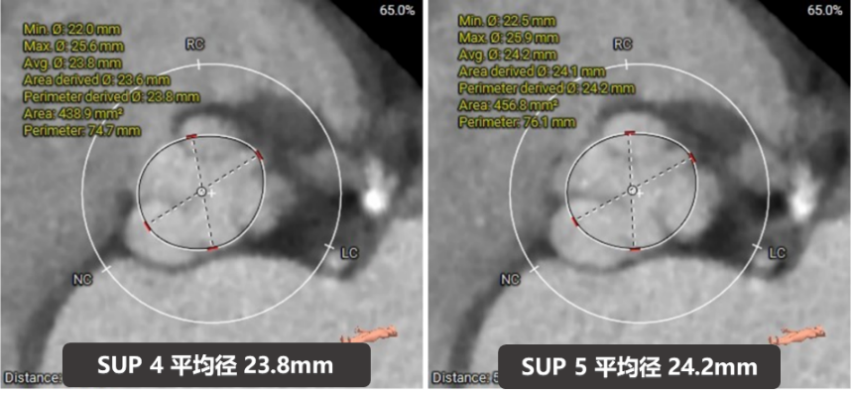

主动脉根部评估

四叶式主动脉瓣,右无间窦体发育较小且窦底高于瓣环平面约6mm;

瓣环上结构测量

收缩期瓣上结构

收缩期瓣上可提供4~6mm筒状区域。

舒张期瓣上结构

舒张期瓣上5mm内区域均小于收缩瓣环径;

该病例的瓣上结构可提供的辅助锚定区域较长,有利于瓣膜的辅助锚定。